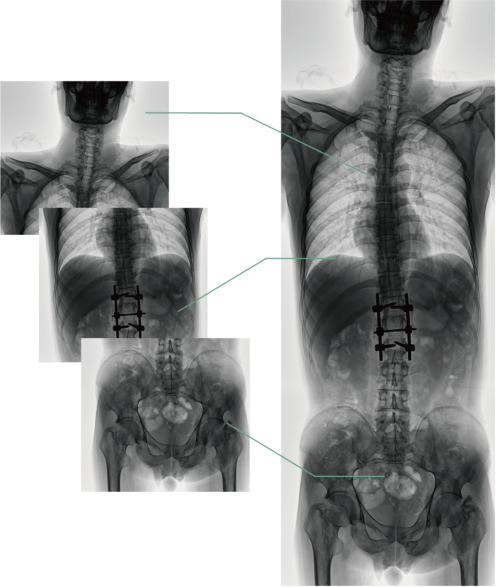

四、圖像自動拼接

圖像自動拼接功能實現全脊柱、全下肢全景攝影,解決在觀察頸椎至尾椎的脊柱側彎或其他病變時不能一次成像的問題,能夠直觀的顯示脊柱和下肢的整體解剖形態及側凸部位。